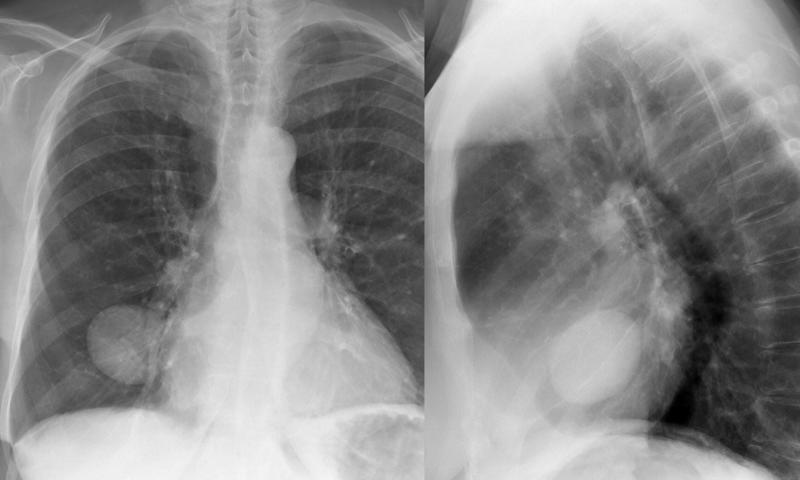

Gallery Pleural fluid in major fissure (pseudotumour)

fluid in major fissure (pseudotumour)